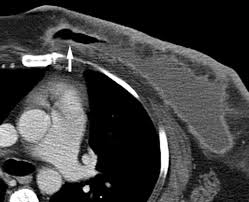

Ct scans can help doctors: If you have a large breast cancer, your doctor may order a ct scan to assess whether or not the cancer has moved into the chest wall. This substance is often called a tracer, because it helps reveal cancer in the body. The scan lets them:learn the cancer's stage. Computed tomography scan, ct scan, cat scan, and spiral or helical ct. 234 views answered >2 years ago Before the scan, you will either drink a liquid dye or be given an injection of dye into a vein in your arm. Breast cancer affects over 200,000 women each year. A pelvic ct scan can be used to detect several types of cancer. Contrast medium is a dye that helps body tissues show up more clearly on the scan. In contrast with bone scans, which are only able to detect bone metastases, pet/ct has the advantage of concurrently imaging other common sites of breast cancer metastases such as the liver and lungs, says lead author patrick morris, a breast cancer specialist at memorial sloan kettering. You are encouraged to drink clear liquids. This helps determine whether or not the cancer can be removed with mastectomy.

In general breast cancer can be detected on a routine chest ct scan regardless of if contrast media is used or not. Several types of cancer can form in the breast, making it the second most common cancer that affects american women. These scans expose you to more. Before a pet/ct scan, an iv that injects a small amount of a radioactive substance will be placed into one of your veins. Long story short i have a ct scan with contrast on 1st june to look for cancer in the abdominal cavity.